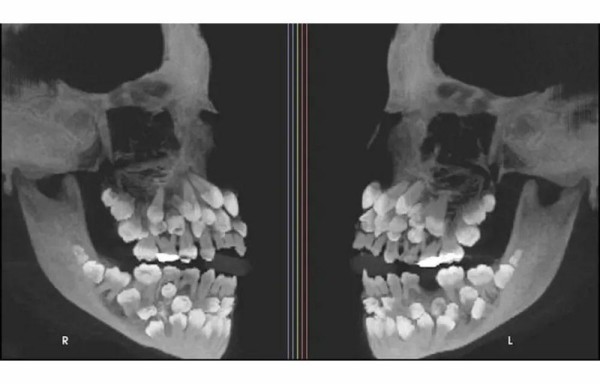

El caso de una niña de 11 años se convirtió en un reto clínico, nació con 81 dientes, padecía "hiperdoncia múltiple".

Fueron detectados 18 dientes caducos, 32 permanentes y 31 supernumerarios, los que debieron ser retirados a través de diferentes procesos : "El tratamiento ortodóncico fue un gran reto por el gran número de piezas a extraer y las alteraciones en las formas', sostuvo uno de los odontólogos que la atendió.